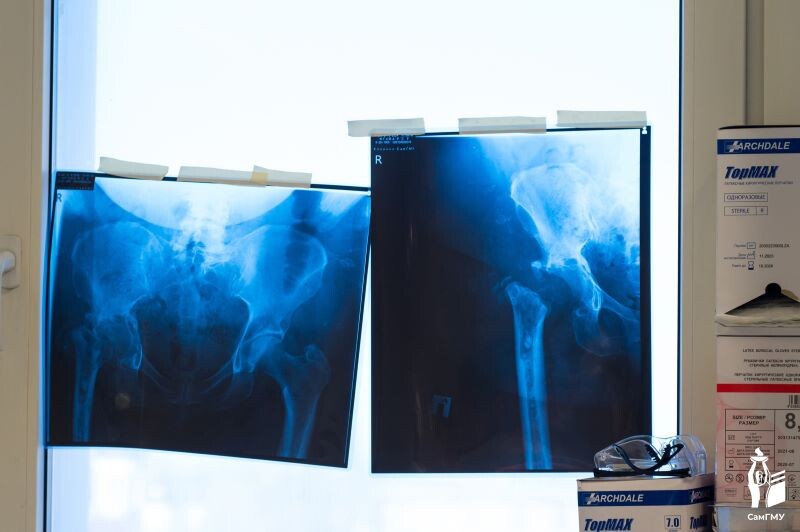

В 2022 году в одном из лечебных учреждений пациентке выполнили операцию по замене тазобедренного сустава. Однако в послеоперационном периоде у женщины неоднократно происходили вывихи головки эндопротеза. Ей провели еще одну операцию, чтобы устранить вывих, но после этого у женщины развилась перипротезная инфекция. В течение следующих лет пациентке провели несколько оперативных вмешательств, но устранить перипротезную инфекцию так и не удалось. Исправить ситуацию взялись в Клиниках СамГМУ. Впервые в Самарской области в ходе ревизионного эндопротезирования тазобедренного сустава пациентке установили индивидуальный эндопротез-спейсер с антибактериальным покрытием. Специальное устройство — спейсер, — схоже с первичным эндопротезом и было изготовлено из костного цемента, в который добавлен антибиотик. Все это позволяет одновременно устранить инфекцию и восстановить утраченные функции сустава и ноги.

Впервые в Самарской области в ходе ревизионного эндопротезирования тазобедренного сустава пациентке установили индивидуальный эндопротез-спейсер с антибактериальным покрытием. Специальное устройство — спейсер, — схоже с первичным эндопротезом и было изготовлено из костного цемента, в который добавлен антибиотик. Все это позволяет одновременно устранить инфекцию и восстановить утраченные функции сустава и ноги.

«В нашей сложной клинической ситуации мы не могли пойти по протоколу двухэтапного лечения, так как спейсер физически было невозможно зафиксировать к кости вследствие ее выраженного дефицита. Поэтому мы приняли нестандартное решение — изготовить и установить эндопротез-спейсер, индивидуально спроектированный на основе данных КТ пациентки», — рассказал руководитель Центра ревизионного эндопротезирования суставов конечностей Клиник СамГМУ, заведующий травматолого-ортопедическим отделением №2, главный внештатный специалист травматолог-ортопед Минздрава Самарской области, д.м.н. Дмитрий Кудашев.

Еще одна важная особенность разработанного эндопротеза — связанность. Это будет служить профилактикой вывихов, риск которых у пациентки очень высок.